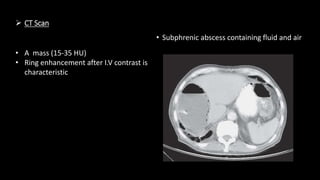

 CT Scan

• Subphrenic abscess containing fluid and air

• A mass (15-35 HU)

• Ring enhancement after I.V contrast is

characteristic